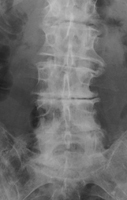

Diagnosis:Degenerative disk disease Discussion:The presence of a linear radiolucency in the disk space (vacuum phenomenon) is a typical finding of degenerative disk disease. It is often associated to other findings of degenerative disk disease such as disk space narrowing and endplate sclerosis. Gas in the disk space is rarely associated to disk space infection. References: